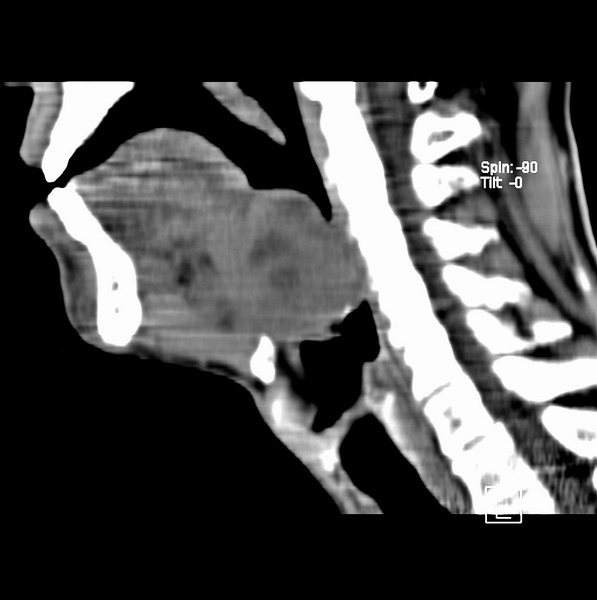

男、60、舌根肿物。

舌垂直肌和横肌影处肿块影,边缘不规则,咽腭扁桃体及舌下间隙脂肪影消失,病变侵及口咽。

考虑-----舌根癌

舌跟软组织肿块,较大有坏死,钙化。结合年龄一般是恶性肿瘤。

舌根部较大软组织肿块,其内见坏死低密度区及钙化影;考虑舌根癌可能。